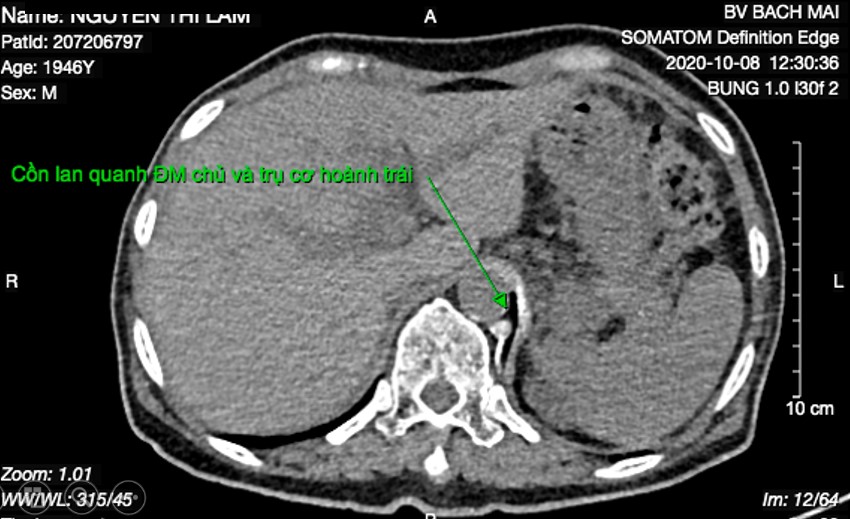

Cồn tuyệt đối lan qua trụ có hoành trái